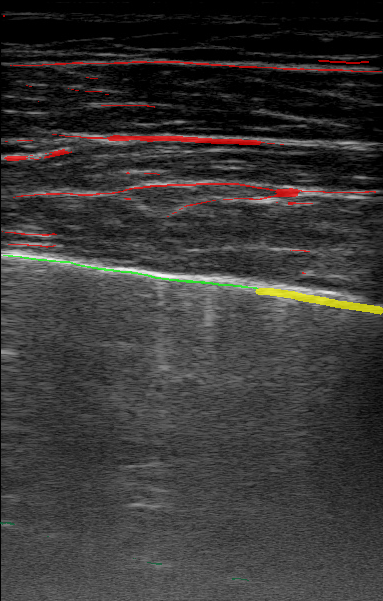

Figure 4 shows example segmentation outputs for the same test example shown in Figure 1. Each image represents the segmentation output of a model trained with the relevant confidence threshold. Similar to the expert labels, the segmented clinical features tend to get more refined as the confidence threshold increases. The 100% model tends to over-segment features, while the 100% model misses some features entirely, as expected.

| LUS Image | |||||||

|---|---|---|---|---|---|---|---|